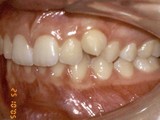

Zkřížený skus, předkus, nedostatek místa pro špičák. Léčba pomocí aparátu Hyrax a dále fixními aparáty v obou čelistech s jumping aparátem. V ústech přítomné MARA-stopy na dočasnou stabilizaci výsledku.

Před léčbou        Po léčbě

pravo pac2       prava pac2